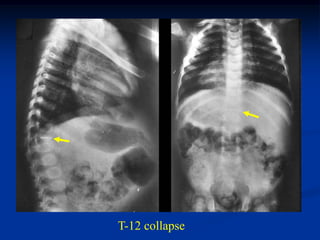

T-12 collapse